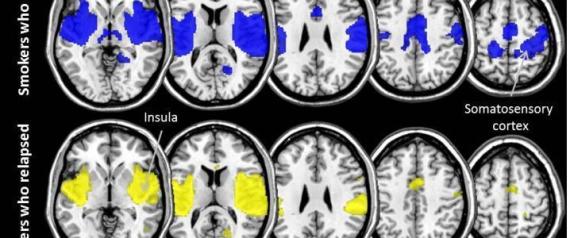

위는 금연에 성공한 사람의 뇌. 아래는 10주 내에 금연에 실패한 사람의 뇌다.

연합뉴스에 따르면 그 결과 금연에 성공한 그룹은 보상을 관장하는 뇌 부위인 섬엽(insular)과 충동 행동을 통제하는 뇌 부위인 체성감각 피질(somatosensory) 그리고 이 두 부위를 연결하는 신경회로의 기능이 금연에 실패한 그룹에 비해 훨씬 강한 것으로 밝혀졌다고 한다.

이 매체는 또한, 금연에 성공한 사람들의 이러한 뇌 기능 패턴은 흡연량과 관계없이 강하게 나타났지만, 금연에 실패한 사람들은 이러한 특정 뇌 부위의 활동이 약했다고 전했다.